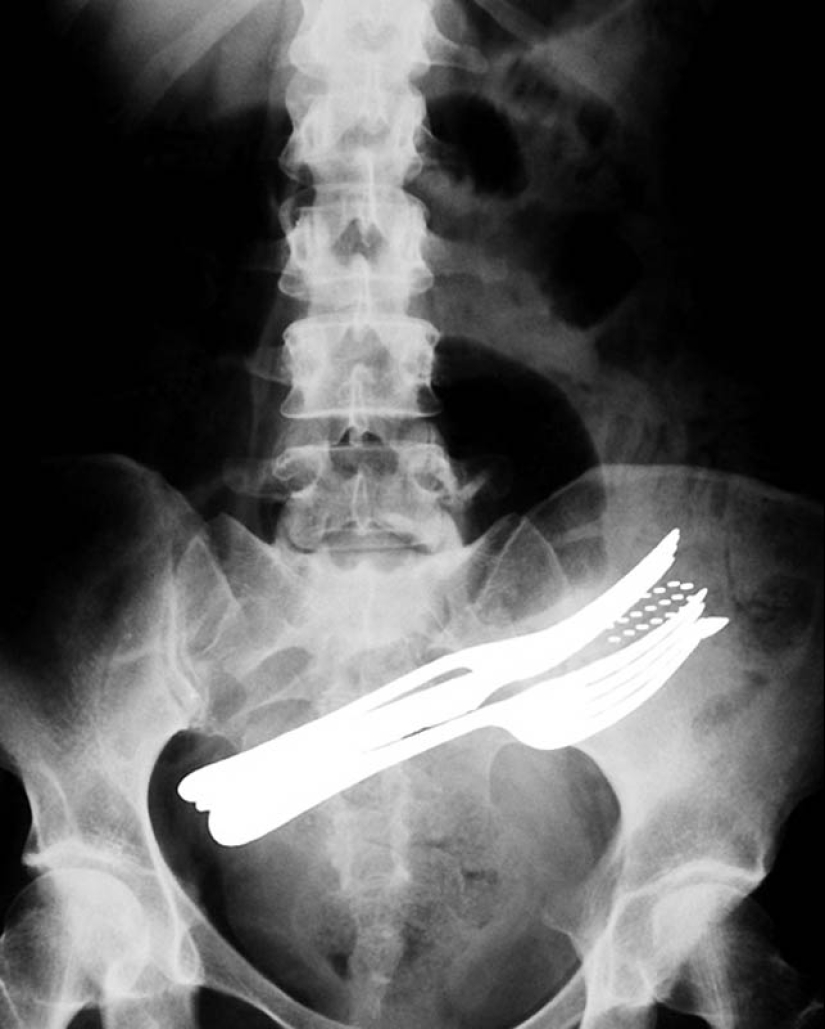

2. The stomach of a patient who has swallowed two forks, a ballpoint pen, and a toothbrush.